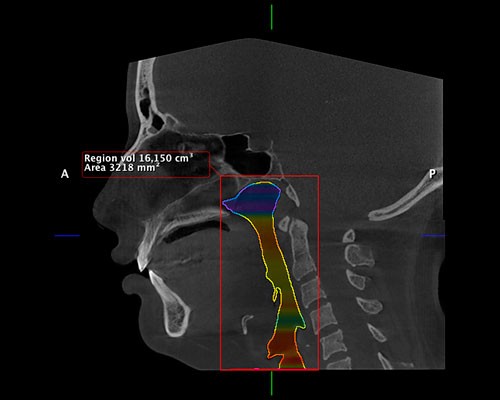

Exclusivo Sistema de Fotografía 3D disponible para todos nuestros clientes. IDM y Planmeca son pioneros en introducir este tipo de concepto en el Perú y consiste en la adquisición de una fotografía 3D sin necesidad de emitir radiación.